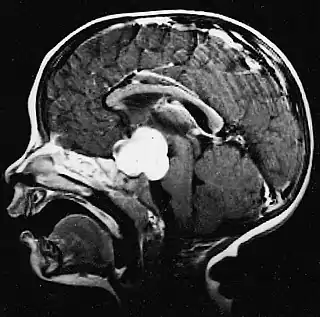

Este tumor se presenta generalmente como una lesión circunscrita y bien delimitada, de crecimiento lento y puede ser sólido o quístico.[2] Suelen apreciarse con facilidad en las imágenes de TC y RM. Los quistes pueden ser monoloculares o multiloculares, con el nódulo tumoral encapsulado en el interior. El astrocitoma pilocítico generalmente aparece a nivel del cerebelo, tronco cerebral, región hipotalámica, nervios y quiasma óptico, y en general en cualquier área donde haya presencia de astrocitos, incluyendo los hemisferios cerebrales y la médula espinal. La localización más frecuente es el cerebelo.[3]

La RM ofrece una mayor sensibilidad en comparación con la TC, si bien no siempre es fácilmente accesible y presenta contraindicaciones, por ejemplo, no se puede utilizar en pacientes con marcapasos, prótesis incompatibles con el campo magnético, clips metálicos, etc. En las imágenes de TC y RM el astrocitoma pilocítico aparece como un tumor con márgenes bien definidos, redondeado, sólido o asociado a macro o microquistes. El 10 % presenta calcificación.[3] La captación de contraste es prácticamente homogénea y muy intensa. Este hallazgo es indicativo de una fuerte vascularización del tumor, aunque en este caso no se considera indicativa de malignidad. En fosa posterior, el diagnóstico diferencial se hace con el meduloblastoma, el ependimoma y el hemangioblastoma, y en la región quiasmática con el craneofaringioma.[9]